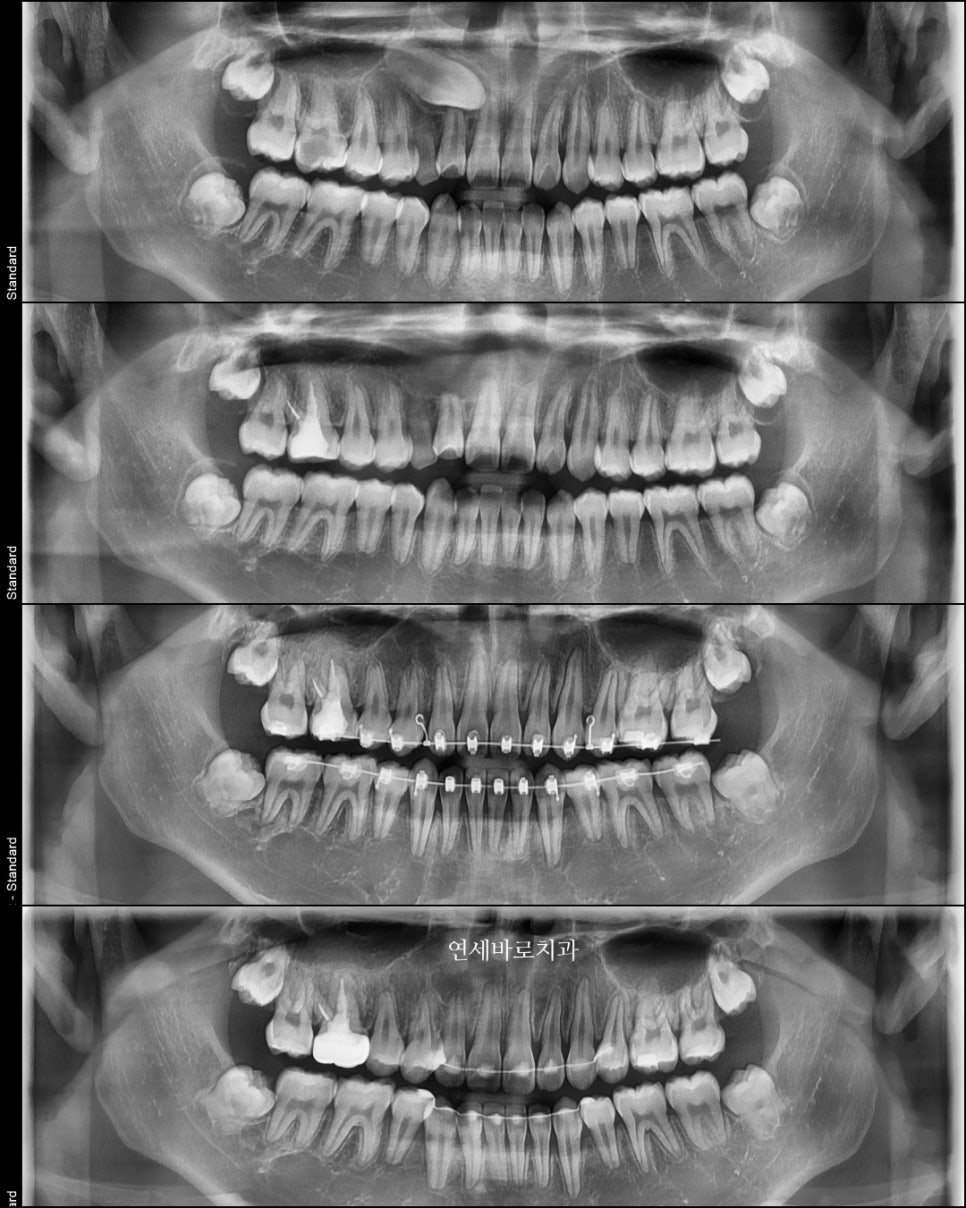

약 1년 반 정도의 치료를 한 아이의 처음과 중간, 그리고 마지막 엑스레이입니다.

매복되어있는 송곳이가 사라졌지만, 끝난 엑스레이를 보면 크게 어색한 것을 모르실 수 있습니다.